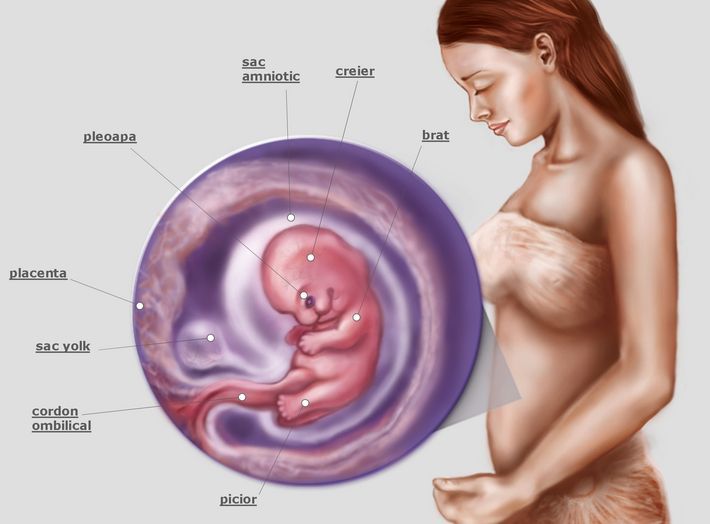

Тошнота на 37 неделе беременности: причины и рекомендации